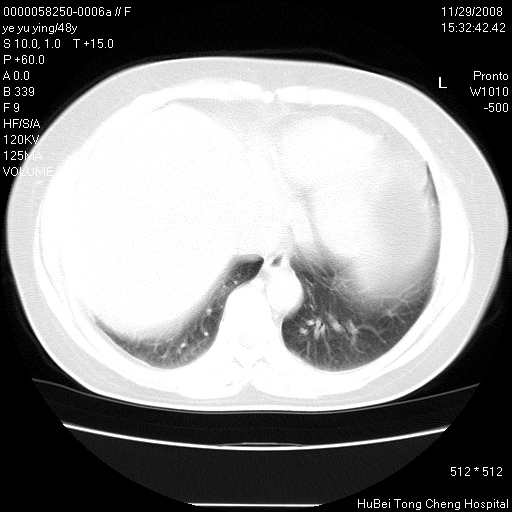

以下是引用zsl6918在2008-11-29 21:47:00的发言:[br]恶性肿瘤病史,转移瘤首先考虑。脂肪肝,胆囊结石。

以下是引用huenhao在2008-11-29 22:11:00的发言:[br]脂肪肝,胆囊结石。左肺病灶建议定期复查。

以下是引用liuyue在2008-11-30 5:44:00的发言:[br]1.左肺病变,首先考虑感染性病变,转移待排;建议治疗后复查。[br]2.肝脏密度普遍减低,考虑与化疗有关。[br]3.胆囊结石.